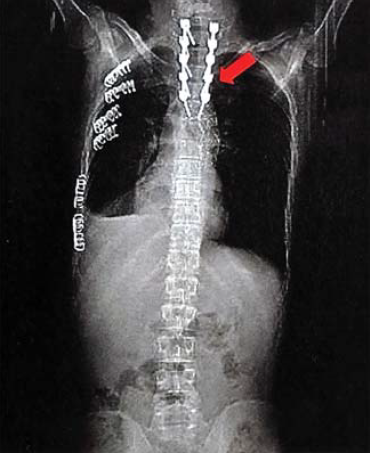

10. ábra.

A lumbalis gerinc rögzítése után az aorta laesio megoldását halasztottan végeztük.

11. ábra.

A stent graft beültetés során végzett DSA az aortasérülés okozta álaneurysmát mutatja.

12. ábra.

A stent graft beültetése után az aorta kontúrja kiegyenlített, az álaneurysma szájadéka lefedésre került.

Neurológiai vizsgálattal petyhüdt alsó végtagi paraplegia volt kimutatható. Tudata visszatért. 24 órán belül, keringési paramétereinek stabilizálása után, stent graft implantatiot, majd másnap ThX-LII segmentumban transpedicularis gerincrögzítést végeztünk (10.,11., 12. ábra). Paraplegia mellett lábszártörését egy héttel később lemezes osteosynthesissel oldottuk meg. A postoperativ szakban septicus szövődmények alakultak ki mind lágyrész sérüléseinek mind gerincműtétének területén. Hosszas antibiotikus kezelés mellett septicus állapota rendeződött. Parapareticus állapotban került vissza a beküldő kórházba rehabilitatio céljából. A betegek és ellátásuk adatainak összefoglalását I, II és III táblázat mutatja.